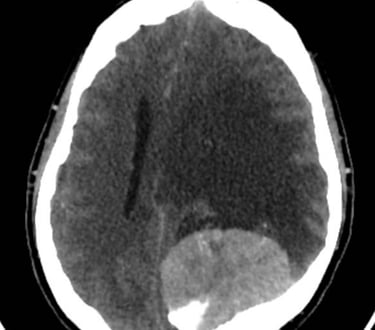

Neurocirugía

Hidrocefalia

Tumores cerebrales y espinales

Aneurismas cerebrales

Traumatismos craneoencefálicos

Hemorragias cerebrales